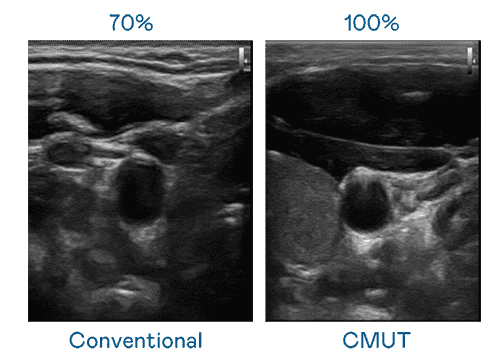

CMUT 技术是一种用电容式微机电元件来产生超音波讯号的技术。。。与传统 PZT 压电式技术相比,,CMUT 频宽增加 30%,,更宽频的超音波讯号让影像解析度大幅提升,,,,是实现高影像品质医疗超音波扫描、、、促进精准医疗发展的关键技术。。

大频宽带来超清晰影像

超音波影像的解析度高低,,,首先取决于探头能发出的讯号频宽。。。牛牛游戏 CMUT 可提供高清晰的超音波讯号,,,,提供高频宽、、、、高灵敏度、、、、影像纹理细节更高的超音波影像,,协助医护人员缩短影像判读时间及利用精准的医疗影像进行诊断。。